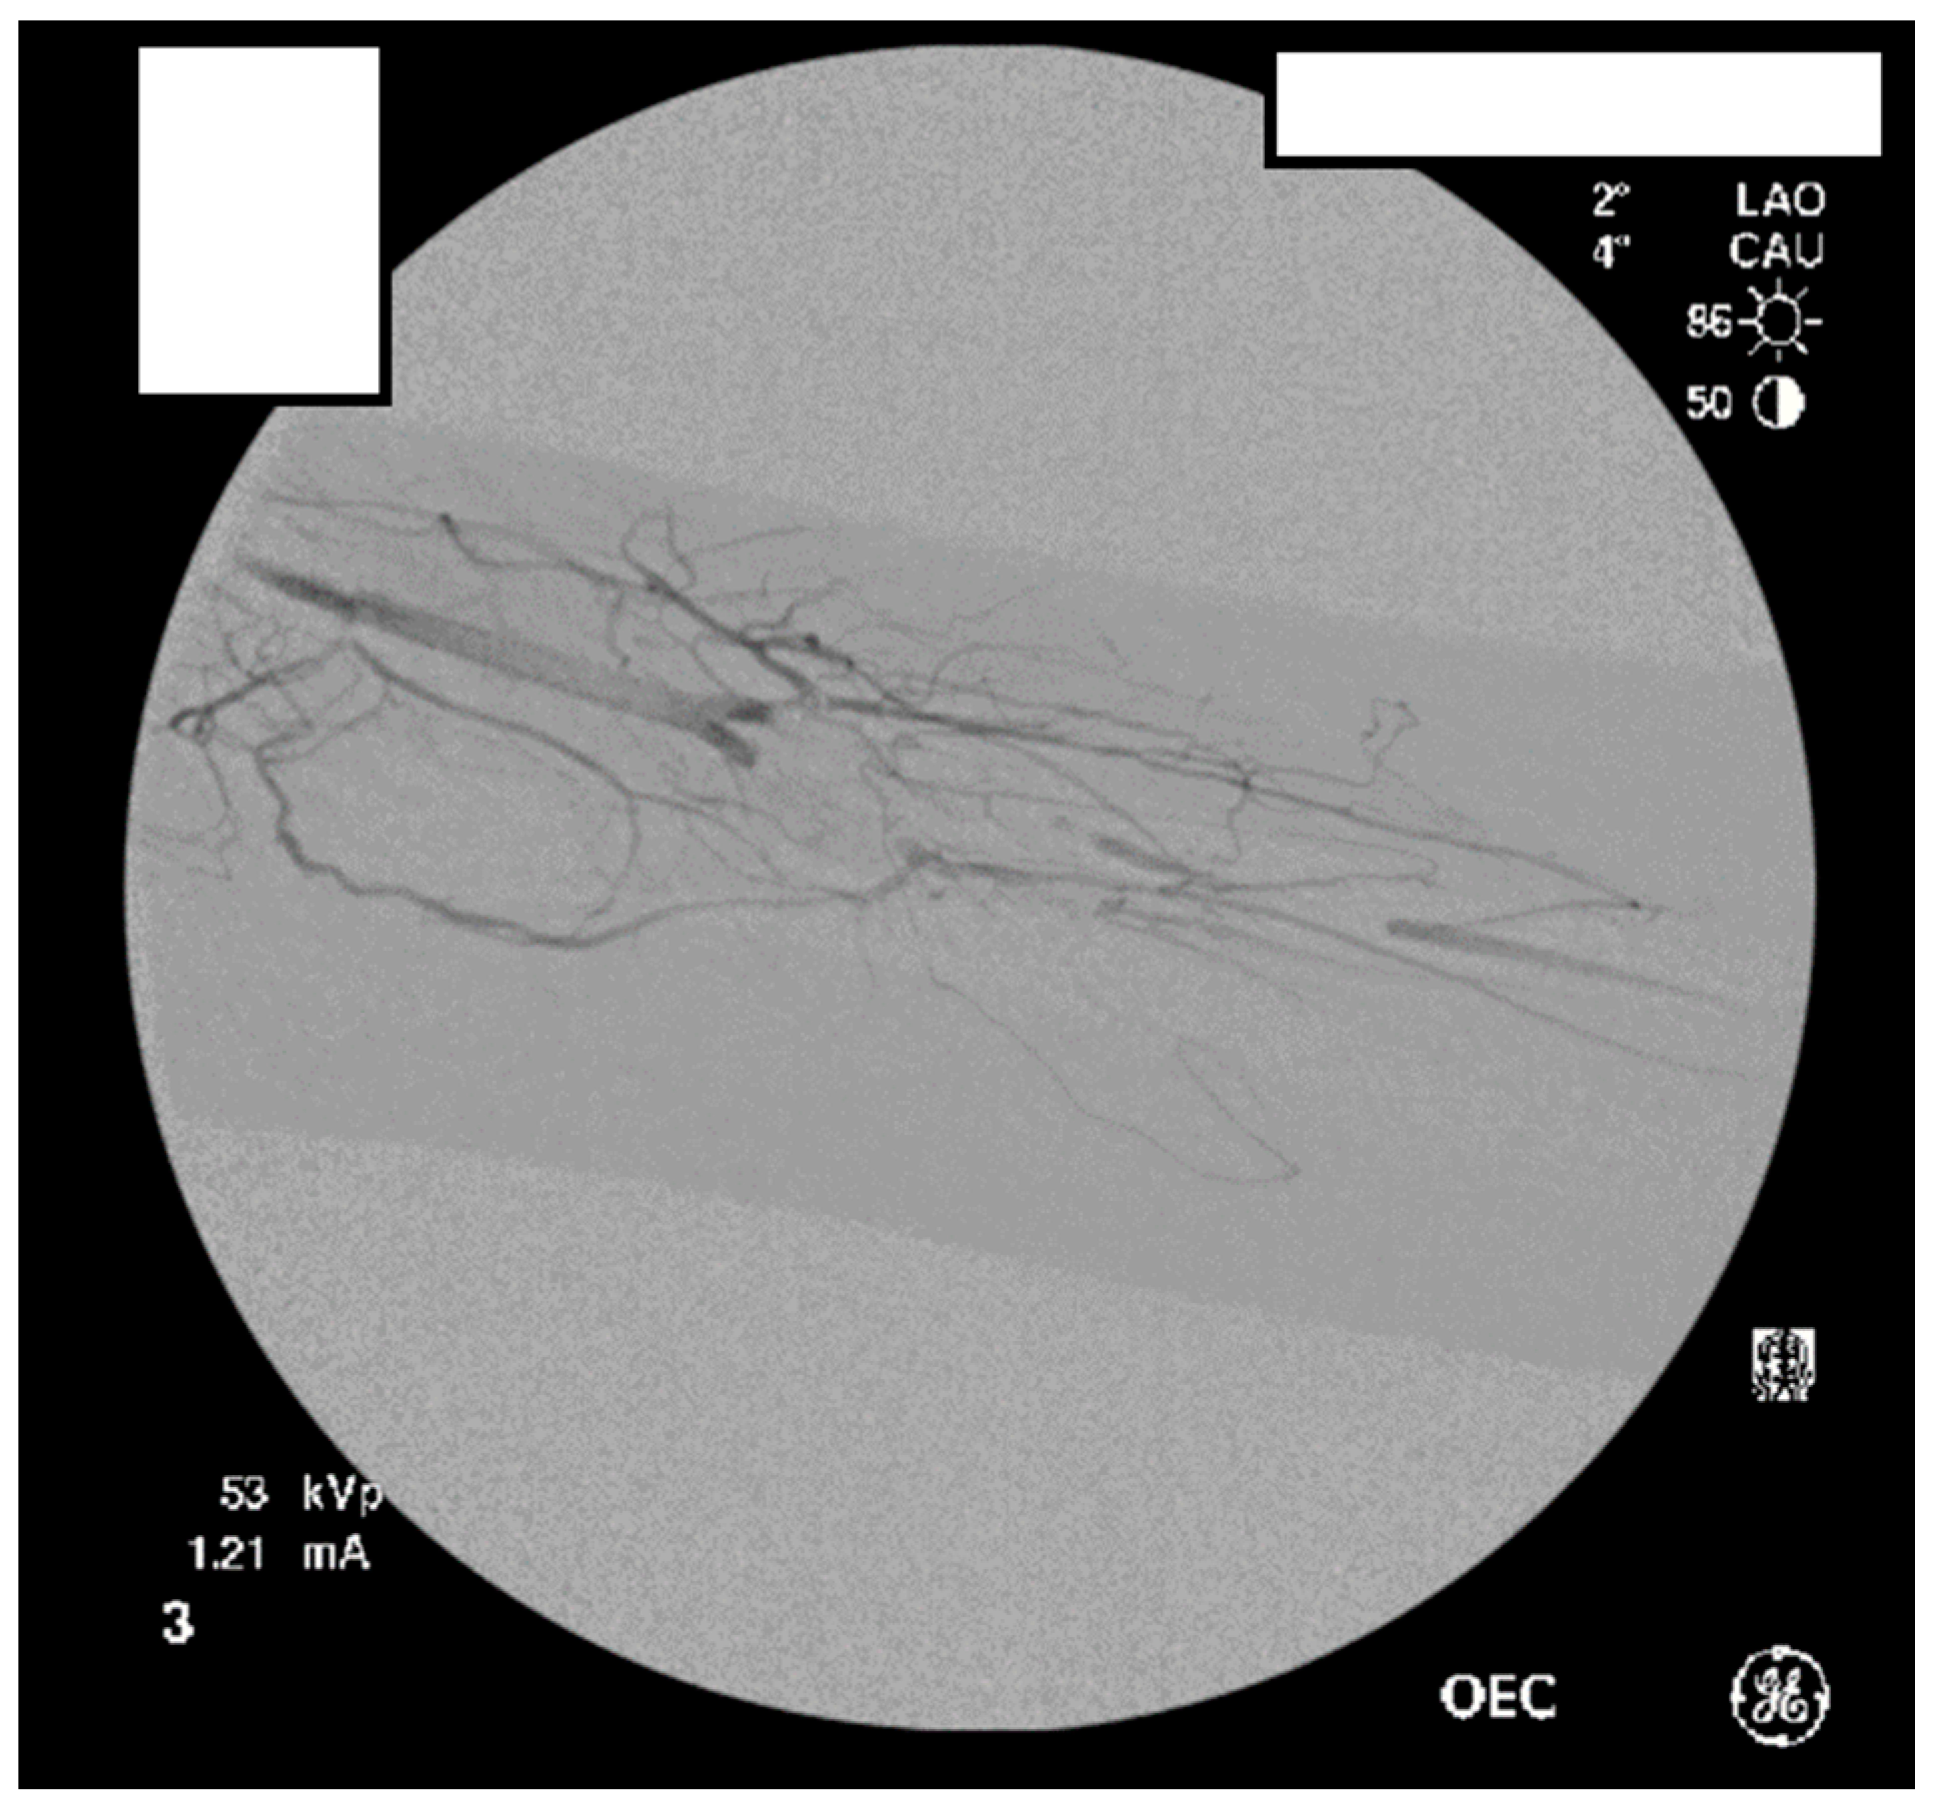

A heparin drip was then initiated, and she was taken to the catheterization lab for thrombolysis. This was carried out with Alteplase for 48 h as the patient had strong collaterals and was not in limb-threat (Figure 7, Figure 8, Figure 9, Figure 10 and Figure 11). However, her radial artery remained occluded. She was then taken to the operating room for thromboembolectomy of the left brachial and radial arteries (Figure 12). She was continued on anticoagulation post-operatively and was discharged.

Distal left arm angiography in an ATOS patient demonstrating an occluded radial artery at the origin and ulnar artery at the mid-forearm.

Figure 10.